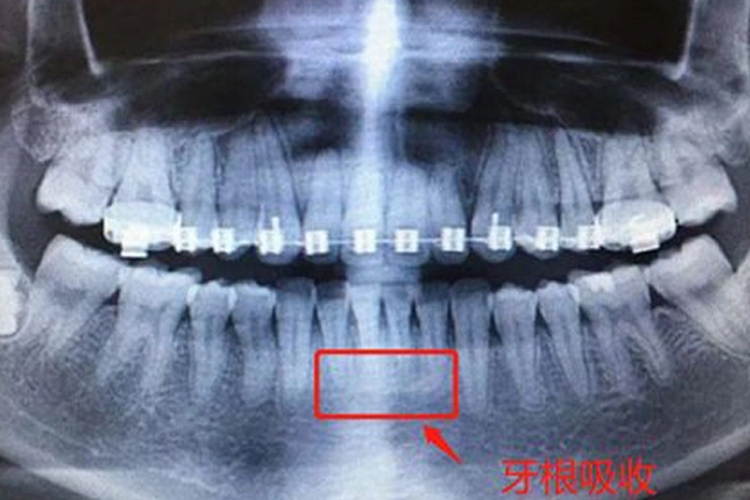

牙齿正畸

牙根吸收主要表现在两方面,一方面是牙根吸收而使牙根变短,另外牙根表面牙骨质甚至牙本质浅层引起吸收,使牙根表面不光滑,呈锯齿状。